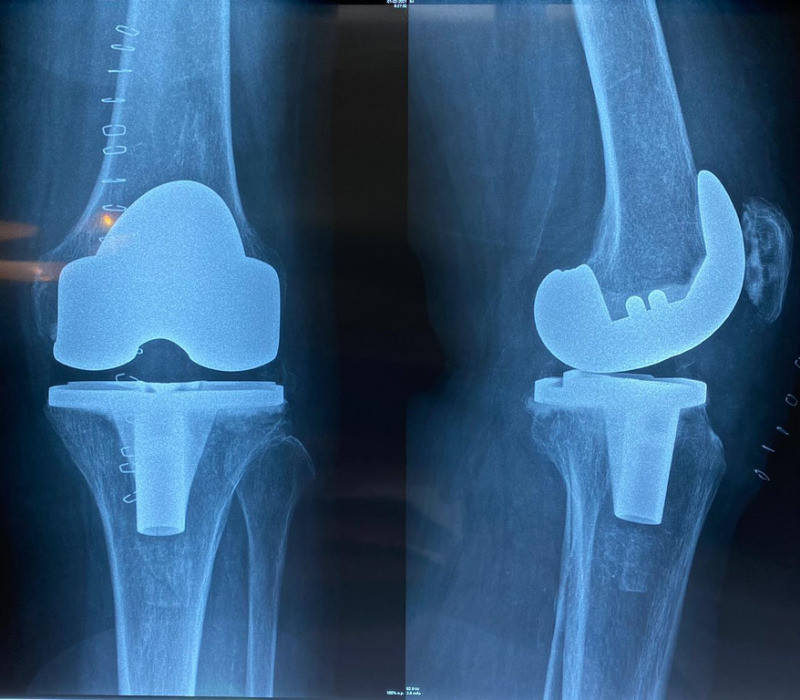

Prótesis total de rodilla

Envíado por Dr. José Israel Flores Hernández